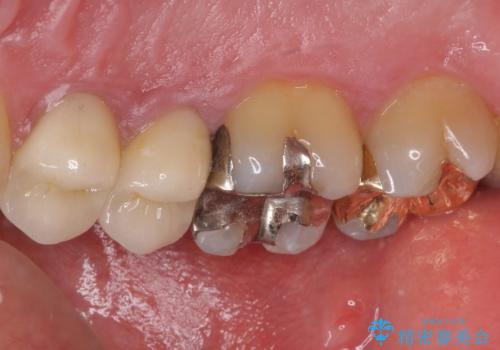

- 上の奥歯に装着されていた銀歯が外れてしまったとのことで来院された患者様です。

強い咬合力により銀歯と歯の間に隙間ができ、その隙間から虫歯となって外れてしまったと想像されました。

銀歯では歯と充填物の固さに違いがあり、再度外れてしまうリスクが高いため、固さが歯と近いゴールドインレー(PGAインレー)にて修復することとしました。